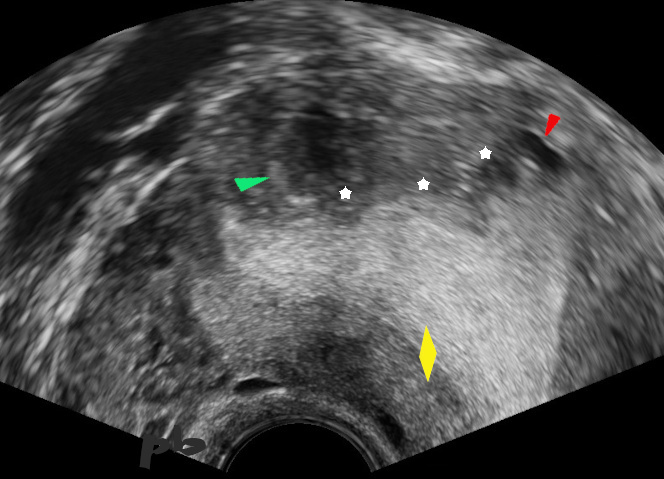

Multiples images hyperéchogènes ( ► ) donnant à l’interface endomètre-myomètre un aspect irrégulier. Elles correspondent à la présence de glandes endométriales dans le myomètre.

Endomètre (★). La ligne cavitaire est bien visible.

Une plage hyperéchogène plus importante, sans flux en doppler couleur (★) : kyste hématique probable.

Multiple hyperechoic images (►) giving the endometrium-myometrium interface an irregular appearance. They correspond to the presence of endometrial glands in the myometrium.

Endometrium (★). The cavity line is clearly visible.

A larger hyperechoic area, without flow on color Doppler (★): probable hemorrhagic cyst.